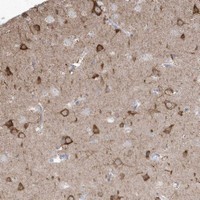

- Immunohistochemical staining of human cerebral cortex with GTPBP8 polyclonal antibody (Cat # PAB22833) shows strong cytoplasmic positivity in neuronal cells at 1:1000-1:2500 dilution.

- Immunohistochemistry (Formalin/PFA-fixed paraffin-embedded sections)